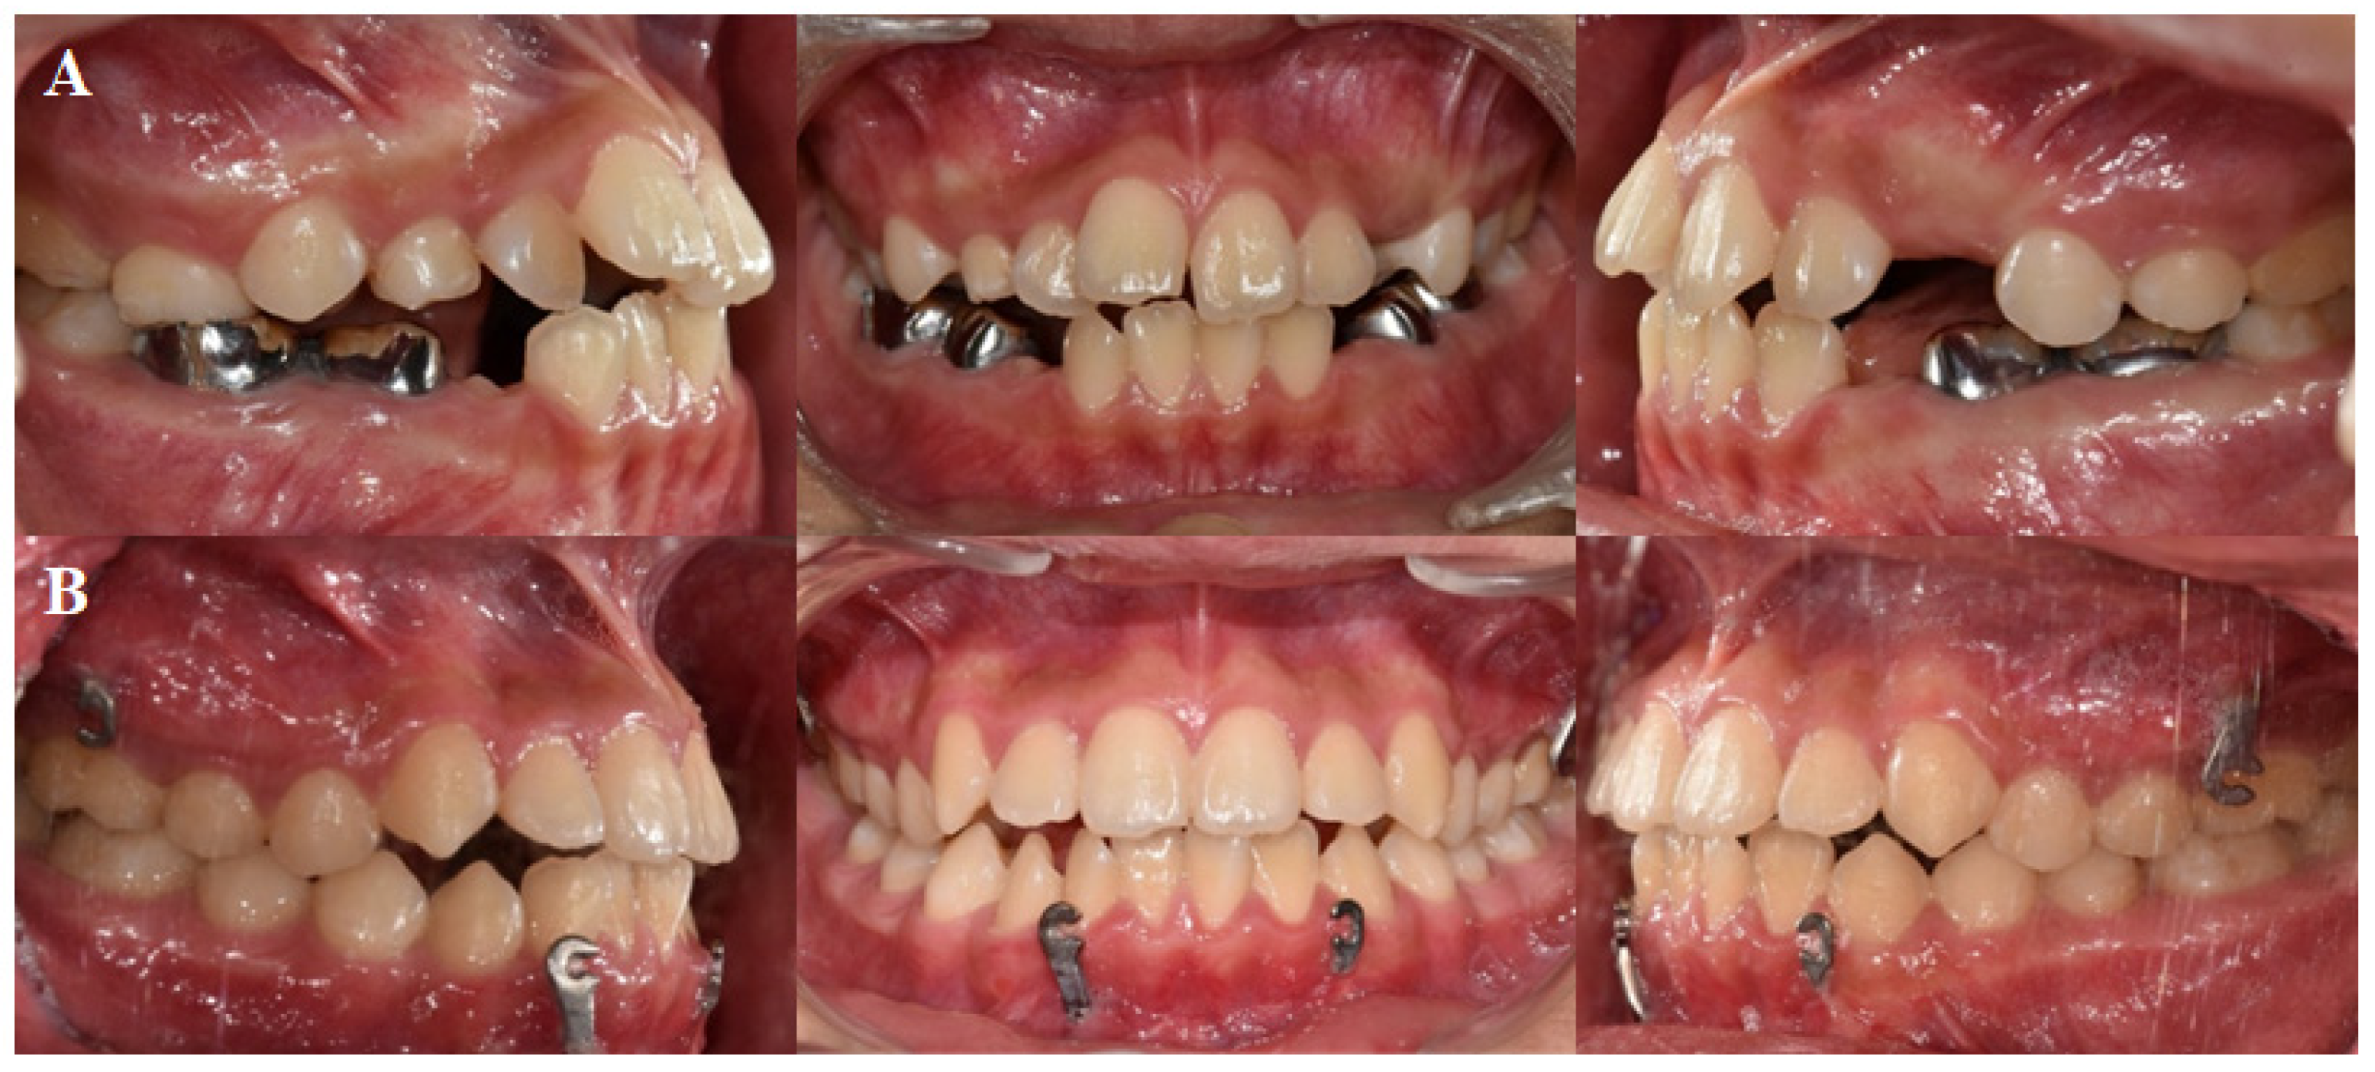

4. Case Presentation

| SNA | 81.6 (3.1) | 77.98 | 84.63 |

| SNB | 79.1 (3.0) | 82.54 | 85.72 |

| ANB difference | 2.4 (1.8) | −4.56 | −1.09 |

| Wits appraisal | −2.7 (2.4) | −7.52 | −3.26 |

| FMA | 29.63 (5.66) | 30.34 | 28.98 |

| SN-GoMe | 36 (4) | 37.1 | 32.72 |

| A point—N Perpend | 0.4 (2.3) | −5.37 | −1.86 |

| Facial Height Ratio | 65 (9) | 61.7 | 66.37 |

| Posterior Facial Height | 85 (5.5) | 76.84 | 90.76 |

| Anterior Facial Height | 127.4 (5.6) | 124.52 | 136.74 |

| U1 to SN | 107 (6) | 123.45 | 120.62 |

| IMPA | 95.9 (6.3) | 78.2 | 78.3 |

| Interincisal angle | 124 (8.3) | 121.2 | 128.32 |

| Upper Lip E-plane | 0.1 (2) | 0.44 | −1.58 |

| Lower Lip E-plane | 0.1 (2) | 2.69 | 0.26 |

| Nasolabial angle | 84.9 (5) | 93.86 | 101.9 |